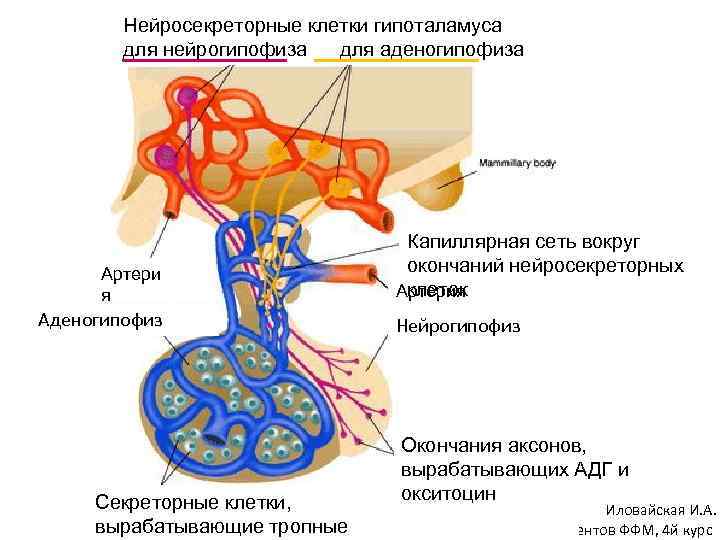

Как работает центр насыщения в гипоталамусе: визуальные иллюстрации